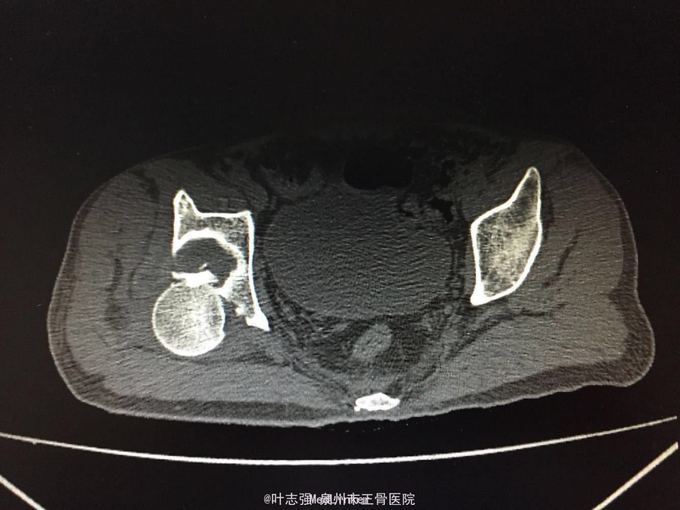

髋臼骨折伴髋关节后脱位ORIF

车祸致左髋部疼痛、活动受限1天。 53岁男性

左髋臼骨折伴髋关节后脱位 行生命支持,股骨髁上骨牵引,

股骨头坏死概率?